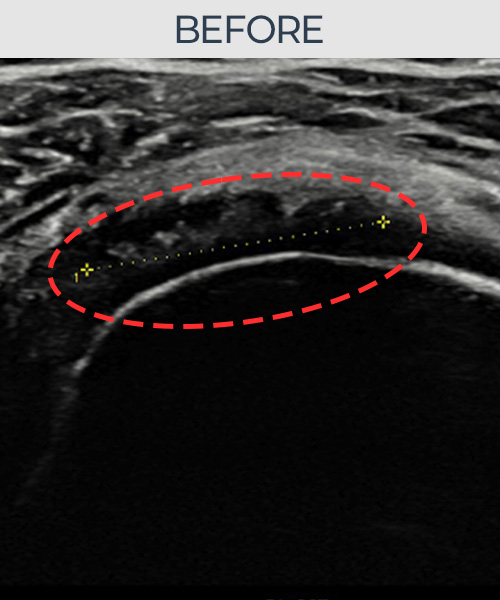

허ㅇㅇ님 · 우측 극상근건 관절면측 부분파열

우측 어깨 통증과 팔 들어올리기 제한으로 내원하셨습니다. 정밀 초음파 검사에서 극상근건 관절면측 부분파열이 확인되었고, 어깨인대 축소봉합술 시행 후 힘줄 연속성과 에코 패턴이 정상으로 회복되었습니다.